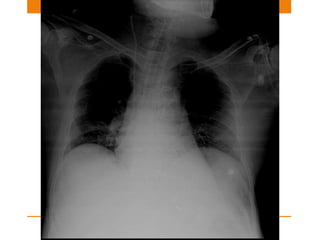

Misplaced lines causes… •Tip too High- Inaccurate right atrium monitoring pressures • Tip too low – In Right Atrium can cause arrhythmia and Cardiac Tamponade • Vessel wall perforation • Infusion of fluid into mediastinum/pleural space • Pneumothorax

Endotracheal tube • USE:Assisted ventilation • The tip of an ETT will be in a satisfactory position if it approximates to the level of the medial ends of the clavicles • Ideal position is 5–7 cm above an adult’s carina when the head is held in the neutral position. • And if carina is not visible in 95% people it is situated at T5-T7 vertebra

Position changes • TheETT can move up or down • Flex the neck and the tip can move 1.9 cm I,e ~2cm downwards. • Extend the neck and it can move 1.9 cm I,e ~2cm upwards. • Rotate the neck and it can move 0.7 cm upwards.

Malposition • Tip ofright main bronchus: 1. Left lung collapse 2. Right upper lobe collapse 3. Right lung overdistension/pneumothorax • Tip in Oesophagus: 1. ETT lateral to tracheal air shadow 2. Oesophagus distended with air 3. Stomach distended with air